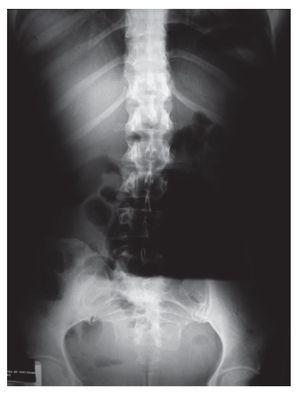

Paciente femenino de 46 años de edad, sin patológicos de importancia portadora de estreñimiento crónico de 26 años de evolución con autoprescripción. Inicia con dolor abdominal súbito de 2 días de evolución localizado en cuadrante inferior izquierdo, tipo cólico, sin náusea ni vómito, por lo que ingiere pancreatina con dimeticona sin mejoría, incrementando el dolor y agregándose náuseas, distensión abdominal e imposibilidad para canalizar gases, motivo por el cual acude a valoración. A su ingreso con vitales normales, con fascies de dolor, actitud forzada por dolor abdominal, mesomórfica. Mucosas parcialmente hidratadas, pálidas, cardiopulmonar sin alteraciones. Abdomen distendido, blando, doloroso a la palpación media y profunda de predominio en cuadrante inferior izquierdo, sin hiperestesia ni hiperbaralgesia. Rebote negativo. Peristalsis de lucha. Extremidades sin alteraciones. En radiografías simples de abdomen se observa distensión importante de colon proximal con nivel hidroaéreo en colon transverso y ausencia de gas en colon descendente y ámpula rectal (Imágenes 1 y 2). Se realiza colonoscopia con diagnóstico inicial de obstrucción colónica, introduciendo colonoscopio hasta una distancia de 120 cm, con lo que se llega a tercio distal de colon transverso impidiendo avanzar más el endoscopio por una zona de estenosis puntiforme, probablemente secundaria a torsión (Foto 1) intentando realizar detorsión sin éxito, por lo que es sometida a laparotomía exploradora encontrando torsión de colon transverso (Fotos 2 y 3) efectuando hemicolectomía derecha con transversectomía e ileosigmoideoanastomosis con engrapadoras, con una evolución favorable, siendo egresada al cuarto día por mejoría.

Imagen 1. Placa simple de abdomen de pie.